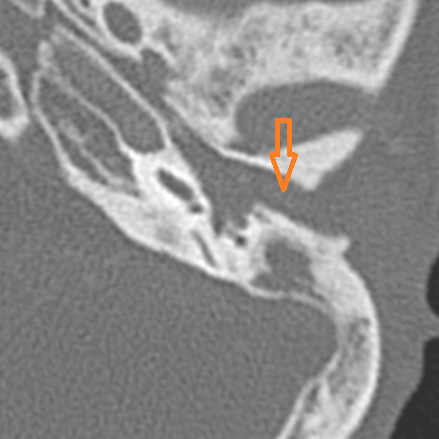

18-year-old female presenting to the emergency room with severe right-sided headache, mastoid region tenderness and swelling and fever, dizziness with possible meningitis. Study is done to look for evidence of coalescent or otherwise complicated mastoiditis as a cause for these symptoms.Exam

Contrast-enhanced CT of the temporal bone and related anatomy with images obtained in the balanced or venous vascular phase to ensure optimal visualization of the dural venous sinuses. 0.5-1.0 mm thick sections were obtained in the axial plane and reformatted 3D and/or in the coronal and sagittal planes and viewed inter actively in 3 dimensions at the computer work station.